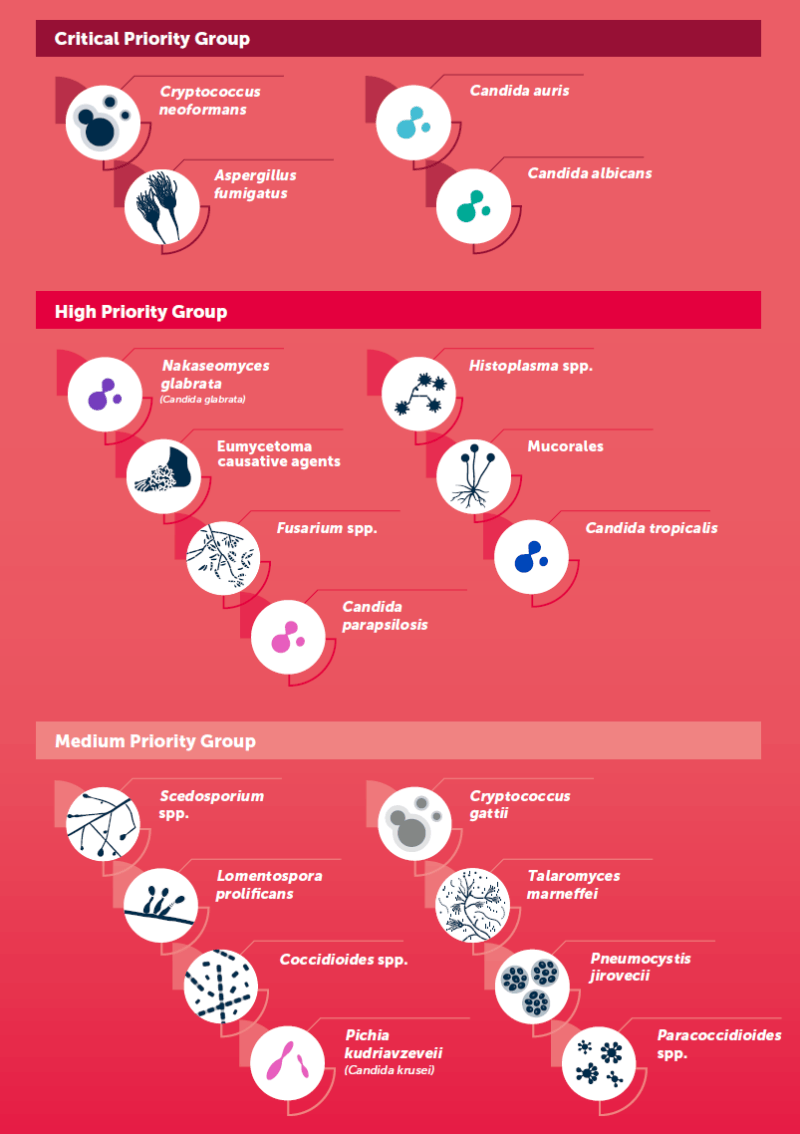

Im Jahr 2022 veröffentlichte die Weltgesundheitsorganisation (WHO) eine Prioritätenliste der Erreger von Pilzinfektionen. Anhand verschiedener Bewertungsparameter wie Letalität, Inzidenzen, Verbreitung und Resistenzen wurden die Erreger in drei Gruppen unterteilt: kritische Priorität, hohe Priorität und mittlere Priorität. C. auris gehört dabei zur Gruppe mit kritischer Priorität,

- Verursacht Pilzinfektionen in Lunge und Gehirn

- Kann lebensbedrohlich werden

- Übertragung durch Einatmen der Pilze

- Verursacht bei immungeschwächten PatientInnen invasive Candidose

- Lebensbedrohliche Krankheit mit hoher Sterblichkeit

- Resistenzen gegen viele Antimykotika und Desinfektionsmittel

- Schimmelpilz

- Überall in der Umwelt zu finden

- Verursacht Aspergillose

- Kann lebensbedrohlich werden

- Befällt v. a. Lungen, auch Gehirn

- Infektion durch Einatmen

- Kommt natürlicherweise im menschlichen Mikrobiom vor

- Bei immungeschwächten Personen brechen Pilzinfektionen aus

- Befällt überwiegend Schleimhäute in Mund, Rachen, Genitalbereich und Verdauungstrakt

- Kann lebensbedrohlich werden

- Nakaseomyces glabrata (Candida glabrata)

- Histoplasma spp.

- Eumycetoma causative agents

- Mucorales

- Fusarium spp.

- Candida tropicalis

- Candida parapsilosis

- Scedosporium spp.

- Lomentospora prolificans

- Coccidioides spp.

- Pichia kudriavzeveii (Candida krusei)

- Cryptococcus gattii

- Talaromyces marneffei

- Pneumocystis jirovecii

- Paracoccidioides spp